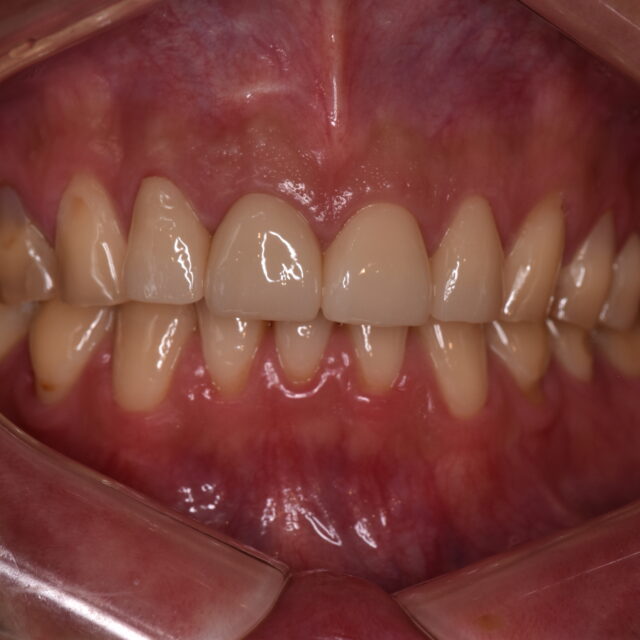

前歯部フルジルコニアクラウン修復🦷 2026年4月6日 TC前田,フルジルコニア,症例 【患者様】 👨 30代 【主訴】 7-8年前に前歯に詰めたプラスチックが欠けたので治してほしい。 【治療計画】 元々の前歯の長さが不揃いであったり、他部位に詰めてあるプラスチックが劣化してきている箇所があ… 続きを読む